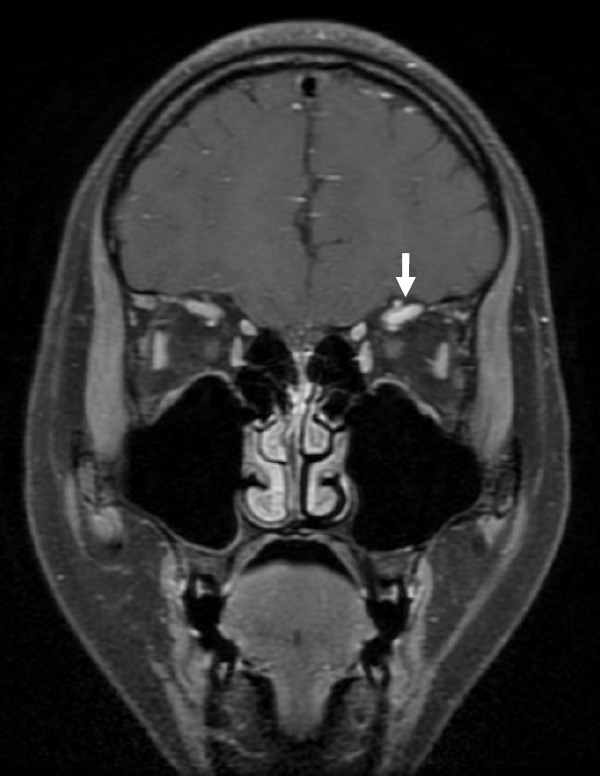

甲状腺眼病是一种自身免疫性疾病,临床表现包括眼睑后缩、突眼、视力下降和斜视,发病率为每10万名儿童中0.79至6.5例。甲状腺眼病在儿童中的发病率为每10万名儿童中0.79至6.5例。虽然报告很少,但发现儿童甲状腺眼病的症状与成人相似,但通常较轻。一名17岁女孩出现复视和左前额感觉减退。其他临床症状包括左眼视力轻度下降、眼球活动受限、上睑下垂和眼睑水肿。根据包括甲状腺功能检查在内的血液检查结果,诊断为巴塞杜氏病,并推测巴塞杜氏病的并发症是甲状腺眼病引起的眶顶综合征,其特点是累及颅神经II、III、IV和VI以及颅神经V的眼部分支。据我们所知,这是首例描述小儿甲状腺眼病眼眶顶综合征的报告,所提供的数据将有助于今后分析非典型小儿甲状腺眼病的临床特征。